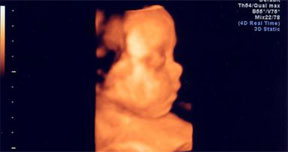

作為準(zhǔn)媽媽的你,擁有一個(gè)健康的寶寶是你唯一的要求。西寧協(xié)醫(yī)院四維彩超設(shè)備,就是為了準(zhǔn)媽媽擁有健康的寶寶而提供的科學(xué)保 障。準(zhǔn)媽媽們通過四維彩超,不僅可以看到宮內(nèi)胎兒打哈欠、伸懶腰、吮手指等等好看的動(dòng)作,還能夠多方位、多角度觀察宮內(nèi)胎兒的生長發(fā)育情況,為早期診斷胎兒先天性體表畸形、先天性心臟疾病提供準(zhǔn)確的科學(xué)依據(jù),并可以直觀的觀測(cè)胎兒實(shí)時(shí)動(dòng)態(tài)活動(dòng)圖像。